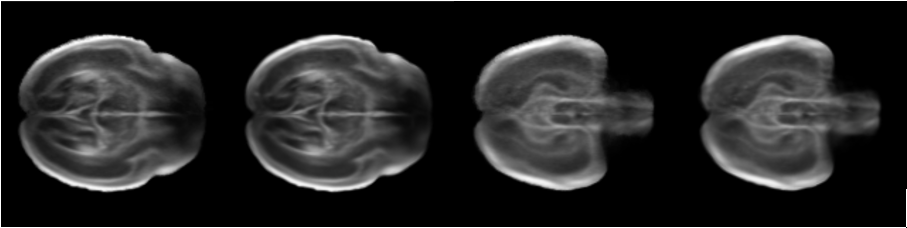

Refer to caption

Figure 1: The results of two groups of fetal brain reconstructions from new perspectives. The left image is the ground truth, and the right image is the reconstructed image.

Figure 1 shows the results of the novel perspective reconstruction of the fetal brain under the 50% slice training condition, where the left image is the ground truth and the right image is the reconstructed image using the proposed method. It can be seen that under sparse slice conditions, the novel perspective image generated by this method is highly consistent with the real slices, and the complex structure of the fetal brain can be accurately reconstructed, demonstrating the ability of this method to maintain structural coherence and detail fidelity under sparse data.